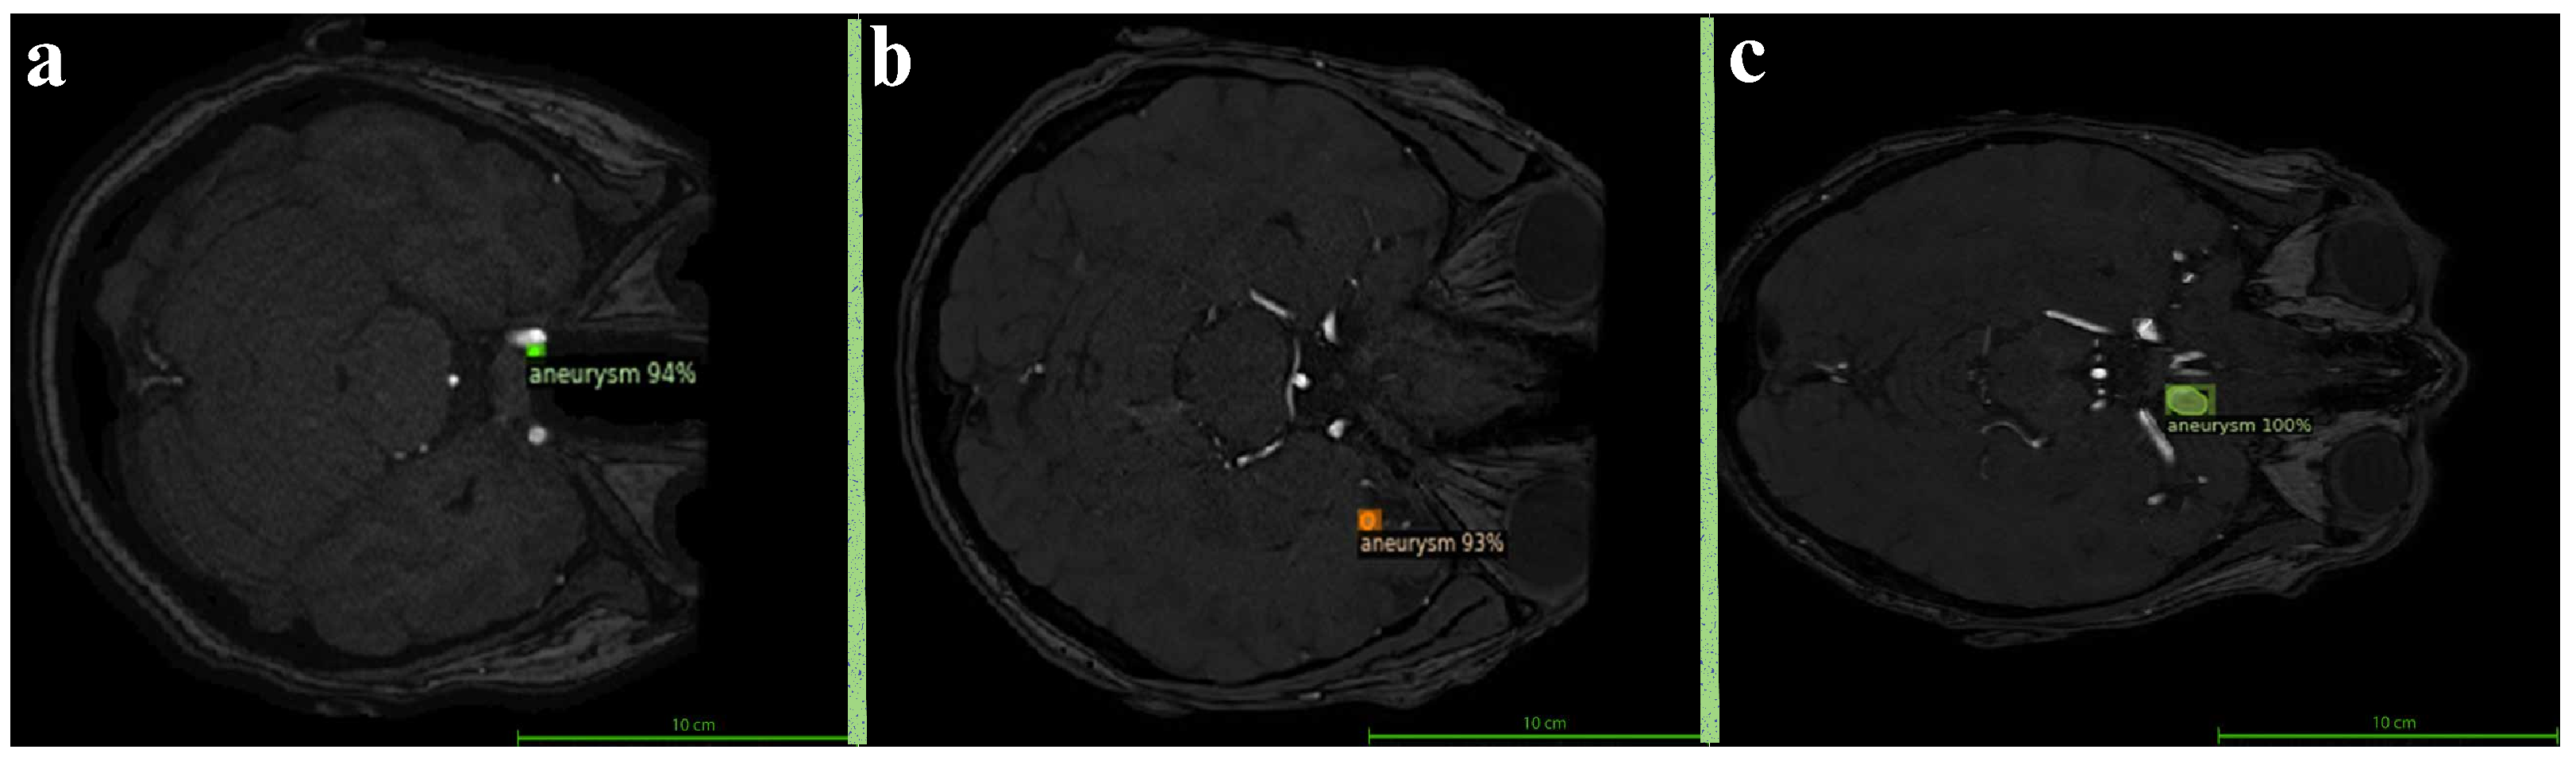

2.2. Manual Segmentation with ITK-SNAP

The segmentation of all aneurysmal cases used in this study was performed manually by an expert radiologist using the ITK-SNAP software version 4.2.0. During the segmentation process, each axial slice of the TOF-MRA images was carefully examined, and the boundaries of the aneurysms were manually delineated using the “Polygon Tool.” As a result of this process, accurately defined mask files were generated for each aneurysmal image as illustrated in Figure 1. Among the 290 TOF-MRA scans obtained from Yozgat City Hospital, 286 cases were labeled as “no aneurysm” after a brief screening. The remaining 4 aneurysmal cases were subjected to detailed segmentation and were manually masked. In addition, all 157 aneurysmal TOF-MRA cases obtained from the OpenNeuro platform were re-evaluated by the expert radiologist and manually re-segmented using ITK-SNAP. As a result of this process, a total of 161 aneurysmal and 286 healthy TOF-MRA images were prepared for use in the study.

Figure 1. Manual segmentation of the aneurysm was performed using ITK-SNAP (version 4.2.0) on the axial view of the TOF-MRA scan. The aneurysm region was manually delineated by an expert radiologist using the Polygon Tool.